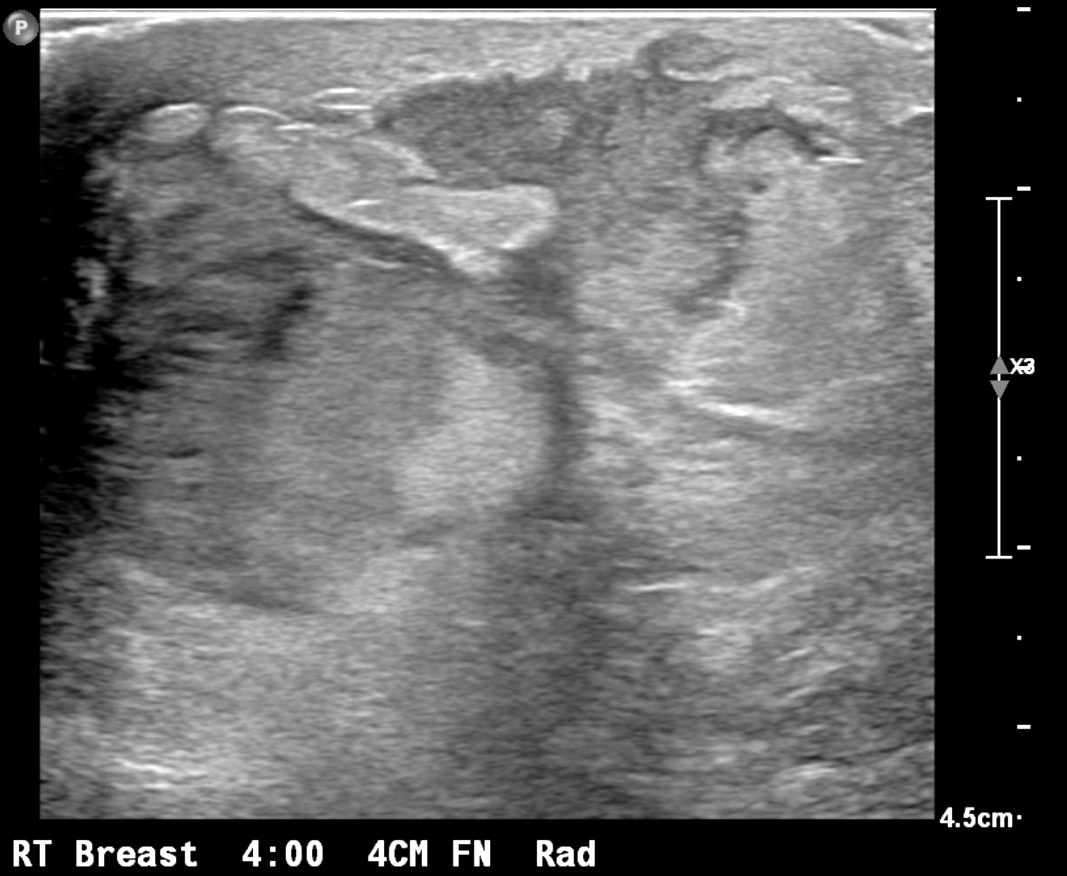

Radiology description

- Ultrasound (preferred modality): abscess shows hypoechoic lesion of purulent material, well circumscribed, macrolobulated, irregular or ill defined with septa and thick echogenic rim (Radiographics 2011;31:1683, Radiographics 2007;27 Suppl 1:S101)

Radiology images